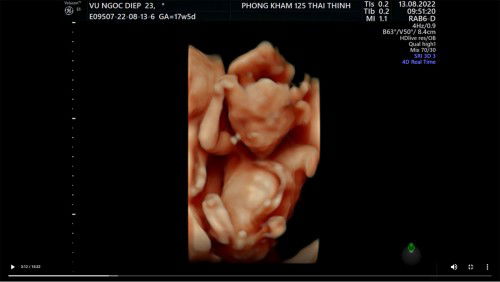

Có khi nào siêu âm sai lệch nhiều k các mẹ ơi 😀😀 36w 2kg5 - sau 1 tuần bé lên có 1 lạng-mẹ k tăng kí luôn ạ 😅😅 E bé 37w nhà em siêu âm có 2kg6 - buồn thối ruột Trong khi con mẹ ăn trứng lộn - đầu tư uống matilia , sữa tươi k đường đều đặn . Nhau thì vẫn độ 0-1 , chả hiểu sao lại k vào con Thế đổ đi đâu hết ạ 😭😭 sốt hết cả ruột Đứa đầu nhà em cũng tầm này sắp đẻ siêu âm bsi bảo có 2kg2 , thế mà đẻ 3kg4 nhưng cách đây 5 năm rồi ... giờ máy móc tiên tiến hơn trước có khi nào vẫn sai lệch nhiều k các mẹ nhỉ 🫥🫥🫥 #Xin_cac_mom_chi_bao #cho_em_xin_ý_kiến_với_ạ #bầu_lần_2